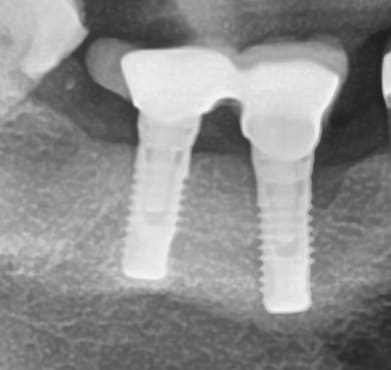

L'un d'entre vous reconnaîtrait-il ces implants? Ils ont été posés il y a une dizaine d'années par un confrère aujourd'hui décédé (qui exerçait à Bagnolet). Je sais qu'il a posé du IDI pendant un temps d'après son ancien prothésiste que j'ai retrouvé mais ce n'en est pas.

La connectique est un hexagone interne avec des vis très larges (compatibles tournevis hexagonal 1.2mm

J'ai déposé les piliers dont voici un exemple. Il s'agit du pilier d'origine, non retaillé.

Ca a été confirmé par SERF, c'est bien un EVL (avec bague à priori)

Et au passage, on a adressé une patiente à mon associé avec un implant en bouche (le praticien qui a posé l'implant est parti du jour au lendemain à l'étranger sans donner d'adresse, bref personne ne connait son système implantaire). Si qq'un a une idée ça serait top, en espérant que ce soit un transgingival. Merci d'avance.